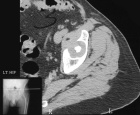

R.H. - 66 year old male presents with LBP for several months. No complaints of hip pain.

Zoom image: Radiological image Radiological image.